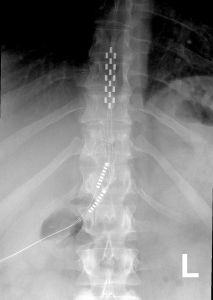

An x-ray of the spine with a stimulator implanted (towards the top of the image, and connecting cords leading off to the bottom left). Source: Wikipedia

A spinal cord stimulator involves a small device being used to apply pulsed electrical signals to the spinal cord. It is generally used for pain relief, but it has recently been tested in a variety of other medical conditions.